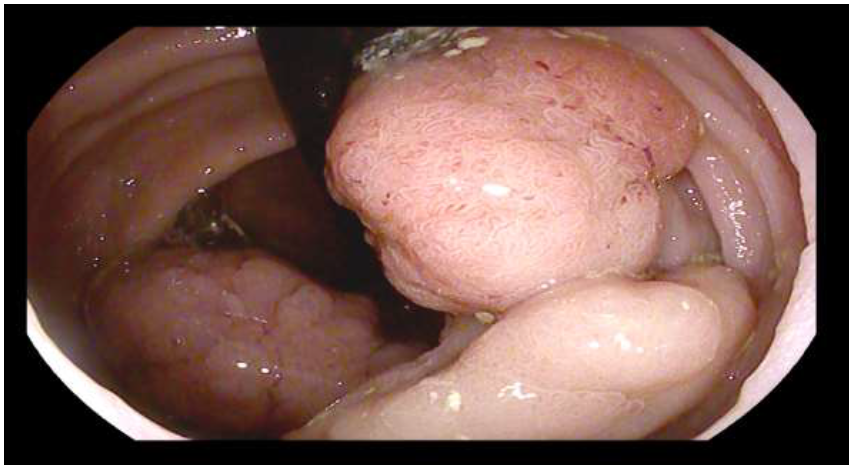

Here we report the case of a 77-year-old ASA 2 woman, who underwent to colonoscopy for sideropenic anemia and positive FIT. Examination showed a rectal granular nodular-mixed laterally spreading tumor (GM-LST) with a dominant nodule of 5 cm and a psudodepressed central area [figure 1,2]. The lesion was extended on the two third of rectal circumference involving the second and the third Huston fold and was judged suspected for invasive carcinoma. The histological examination reported low and high-grade dys-plasia. At total body computed tomography (CT)  no metastatic lesion was detected. Pelvic magnetic reso-nance (MRI) was consistent with T2N0, showing the extension of the lesion nearby the muscularis propria, without a clear distinction plane. In addition, a rectal endoscopic ultrasound (EUS) was requested, confirm-ing the MRI findings. Given the well-known risk of EUS and MRI overstating, as reported by recently re-leased ESGE guidelines [4] and after a gastrointestinal multidisciplinary team (MDT) discussion, the pa-tient was proposed for endoscopic submucosal dissection4. For the procedure, we used a standard   diag-nostic Pentax gastroscope  mounted with a conic distal end cap (ST Hoods, Fujifilm®). First, a mucosal incision was made approximately 5mm around either the proximal and distal side of the rectal lesion, fol-lowed by submucosal dissection using DualKnife J 1.5mm (Olympus®). During the dissection, a deeper submucosal invasion was suspected  beneath  the dominant sessile nodule, where the submucosal space was progressively disappearing for muscular retraction and also for fibrotic reaction [Figure 3]. In this area we moved to the inner circular muscular layer dissection, even using the same small tip knife. The dissec-tion was completed using the Hook Knife J (Olympus) for the lateral part, resulting in complete resection of the lesion, 10x6 cm in size [Figure 4]. The resection phase took 90 min. Hemostasis  was achieved with monopolar  forceps (Coagrasper - Olympus®). The base was sutured using through-the-scope clips and a hemostatic matrix (Purastat®, 3ml) was apposed  to prevent delayed bleeding. Precautionary, the patient was hospitalized for three days and then discharged after uneventful observation. Histological examination of the lesion reported well-differentiated adenocarcinoma (G1) focus over a high-grade dysplasia tubulovil-lous adenoma, no tumoral budding or vascular invasion, absence of tumor on the resection plane and sub-mucosal invasion limited to 500 μm. Histopatology also showed the circular muscular layer on the resection plane of the lesion  [Figure 5]. MDT indication was endoscopic follow-up after 6 months.

Figure 1